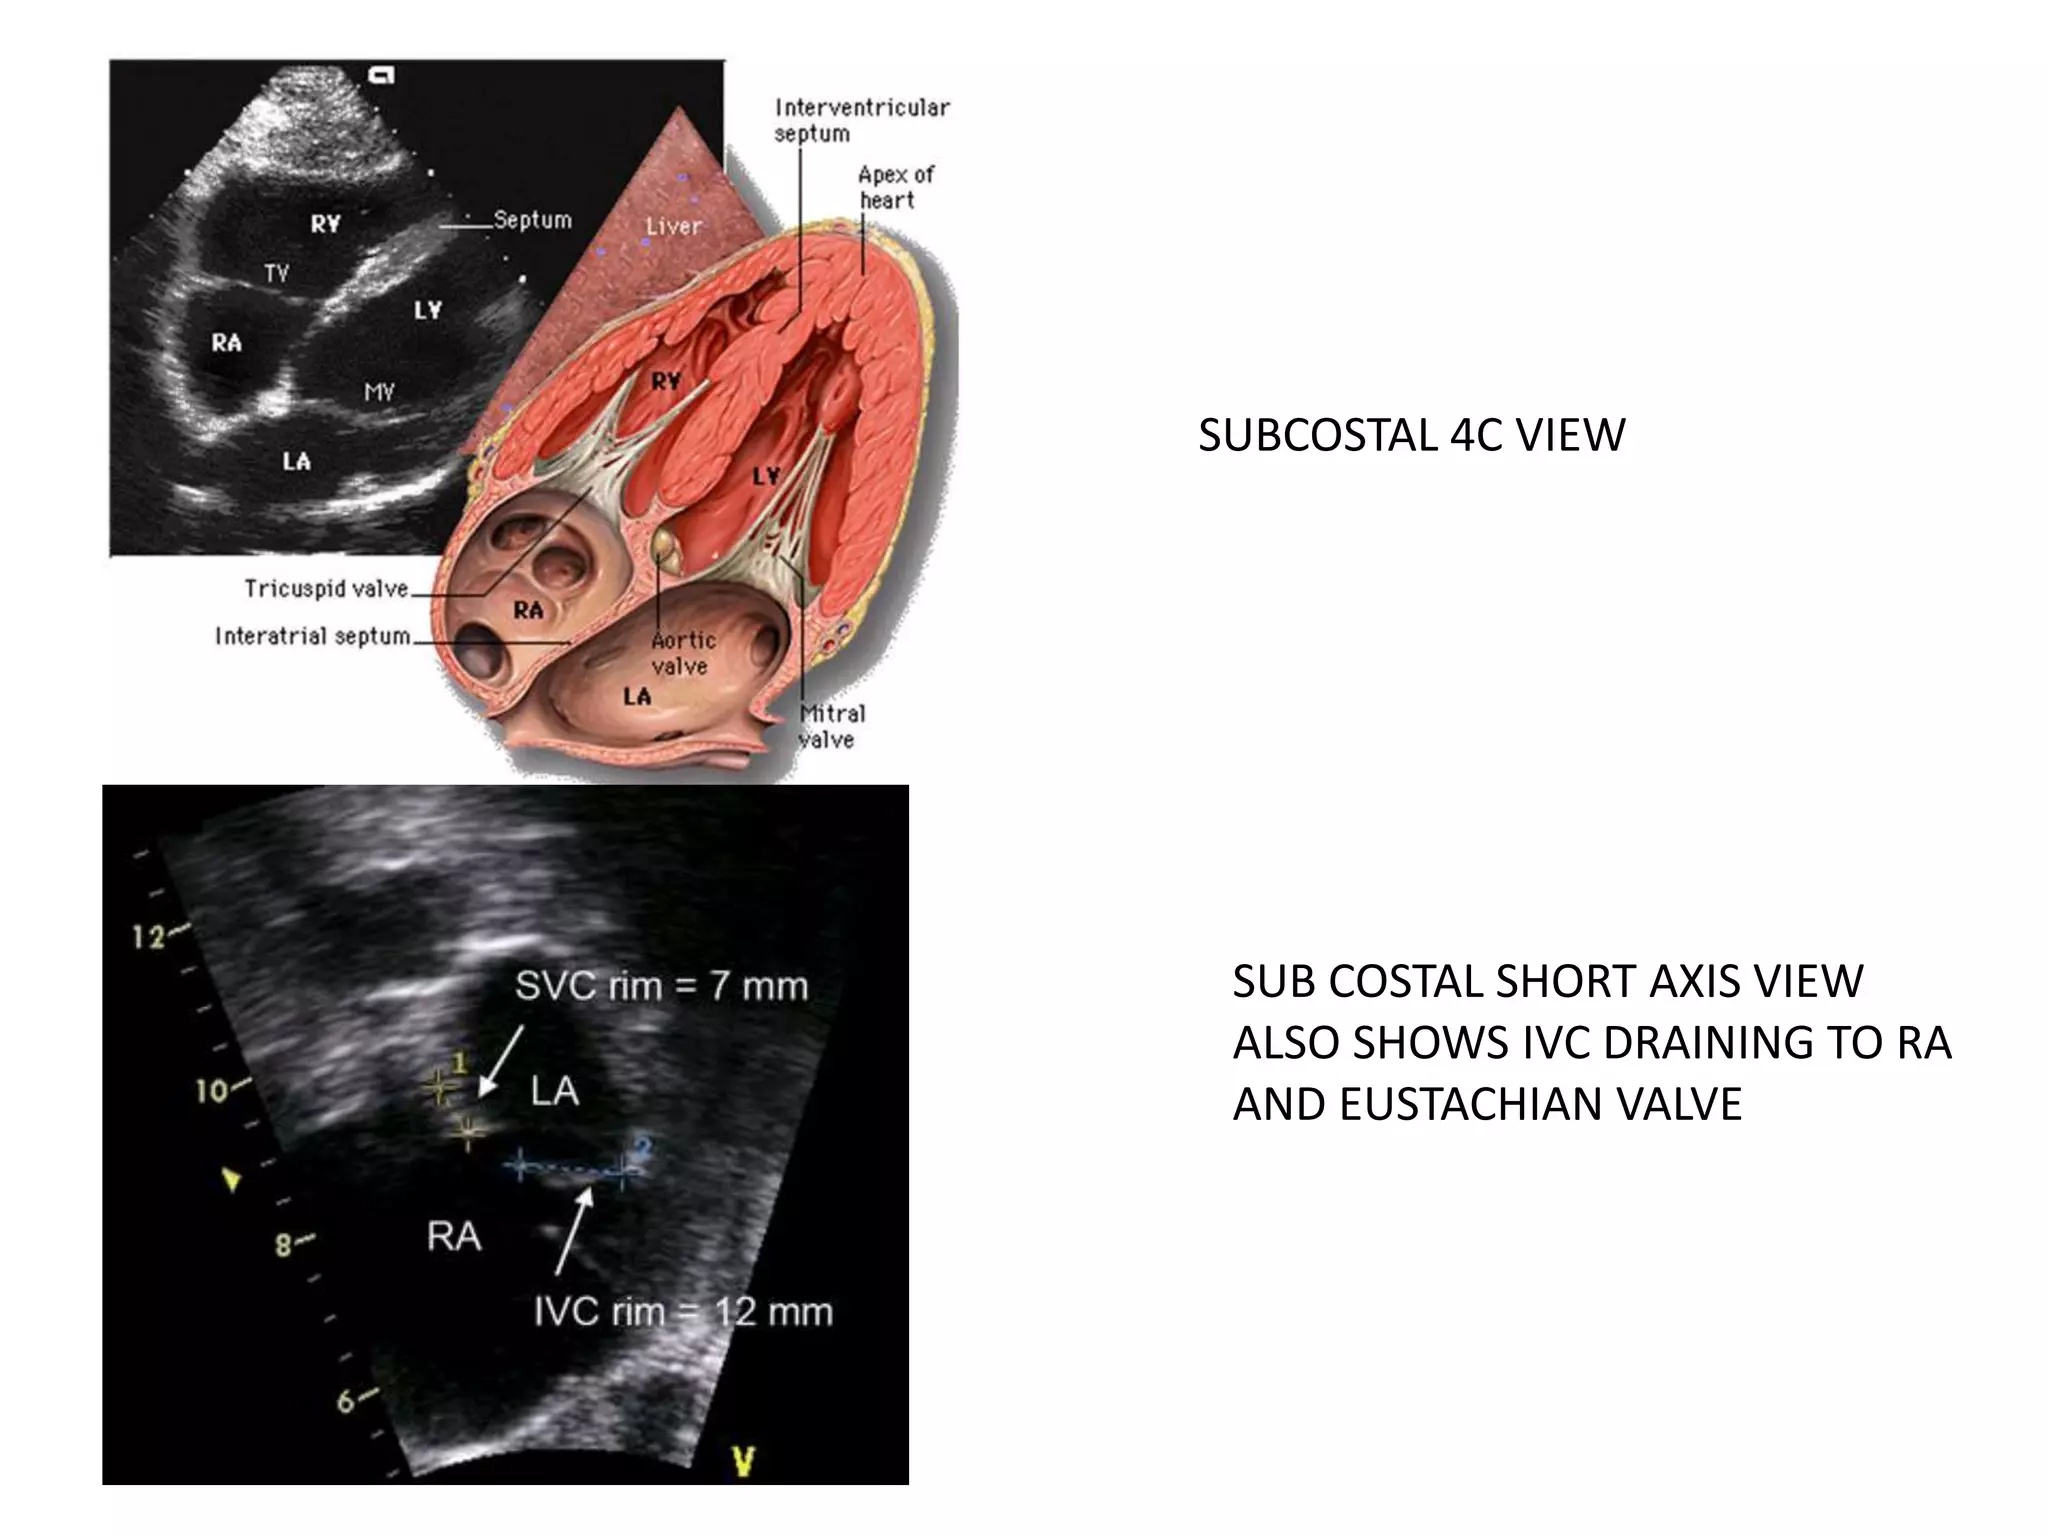

SUB COSTAL 4C VIEW

• Keeps the atrial septum perpendicular to the ultrasound

beam

SUB COSTAL SHORT AXIS

• Index marker at 12o`clock position and sweeping the transducer

SUBCOSTAL 4C VIEW

SUB COSTAL SHORT AXIS VIEW

ALSO SHOWS IVC DRAINING TO RA

AND EUSTACHIAN VALVE

SUBCOSTAL 4C VIEW SUBCOSTAL SHORT AXIS VIEW ALSO SHOWS IVC DRAINING TO RA AND EUSTACHIAN VALVE